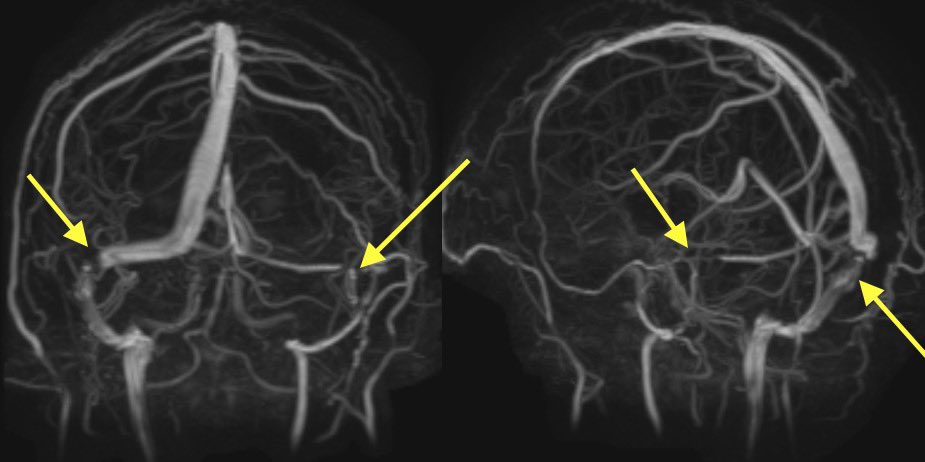

4️⃣Transverse/sigmoid sinus junction stenosis: stenosis may lead to the IIH or the increased pressure may lead to extrinsic compression of the sinuses, which comes first is unknown

Classically, this occurs at the junctions of transverse and sigmoid sinuses or lateral transverse